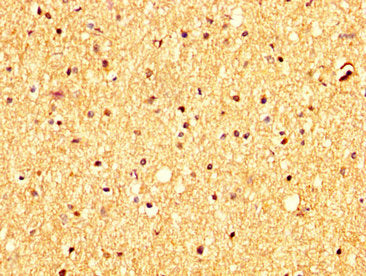

IHC image of RHCG Antibody diluted at 1:300 and staining in paraffin-embedded human brain tissue performed on a Leica BondTM system. After dewaxing and hydration, antigen retrieval was mediated by high pressure in a citrate buffer (pH 6.0). Section was blocked with 10% normal goat serum 30min at RT. Then primary antibody (1% BSA) was incubated at 4°C overnight. The primary is detected by a biotinylated secondary antibody and visualized using an HRP conjugated SP system.